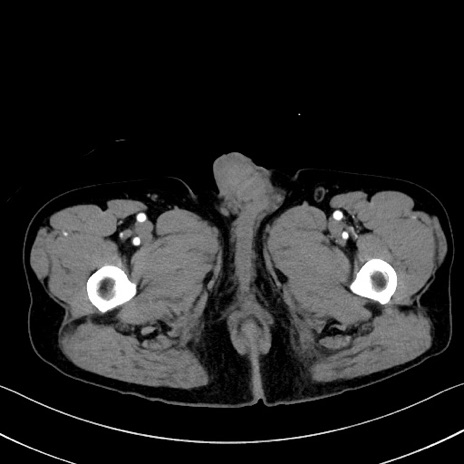

症例35(横断像)

【症例】70歳代 男性

【主訴】腹部膨満、嘔吐

【現病歴】昨日より腹部膨満感出現。本日増悪し、仙痛出現。嘔吐あり、受診。

【既往歴】糖尿病、胆摘後

【身体所見】BP 149/80mmHg、HR 74/min、BT 35.9℃、腹部:膨満、軟、圧痛なし。腸雑音減弱あり。上腹部正中切開瘢痕あり。

【データ】WBC 13500、CRP 1.72